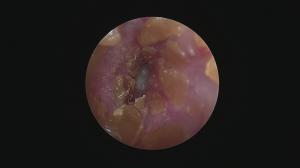

フレブルの耳内は・・・奥に行くほど狭くなります。

また、鼓膜の角度も鋭角で非常に見にくいです。

今回はフレブルの外耳炎

奥の隙間にドロッとした耳漏が認められます。

外来洗浄では限界があるので・・・鼓膜の確認も兼ねて麻酔下での耳洗浄を行いました。